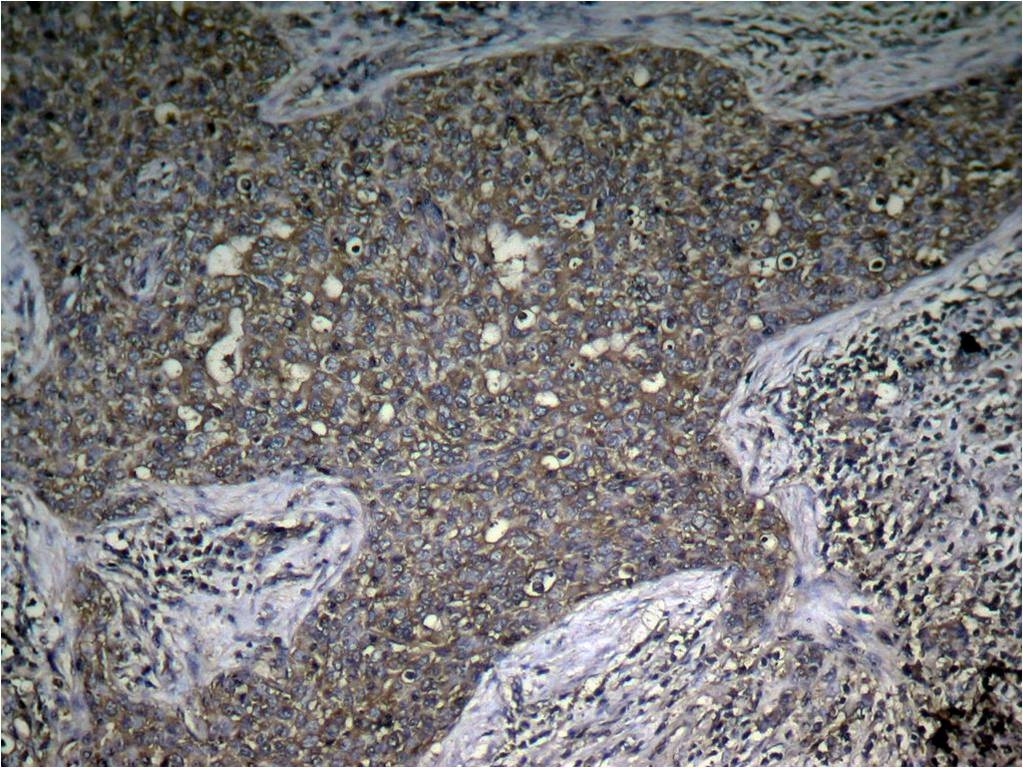

Immunohistochemical analysis of paraffin-embedded human breast carcinoma tissue using mTOR(Phospho-Ser2448) Antibody P40208(left) or the same antibody preincubated with blocking peptide(right).

Immunohistochemical analysis ofparaffin-embedded human breast carcinomatissue using mTOR (Phospho-Ser2448) Antibody P40208